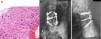

El paciente A, tenía 9 años+10 meses a la edad del diagnóstico (fig. 1). Inicialmente acudió a consulta por dolor lumbar irradiado a miembro inferior derecho. Se realizó TC y RMN, cuyo diagnóstico más probable fue de osteoblastoma localizado en la lámina derecha de L5, rompiendo la cortical, invadiendo el conducto raquídeo y desplazando el saco tecal, confirmándolo posteriormente mediante biopsia. Por este motivo, no se aplicó el protocolo neoadyuvante habitual utilizado en nuestro centro, ni se planteó una resección en bloque inicialmente, sino que se realizó una primera cirugía con resección intralesional (exéresis de masa tumoral+laminectomía L5). Tras analizar la muestra intraoperatoria se comprobó que la tumoración era un osteosarcoma y se clasificó como un Enneking IIB, WBB BCDE zonas 9-12 y tipo 4 según la clasificación de Tomita, e histopatológicamente como un Broders II. Se comenzó tratamiento quimioterápico (protocolo de la Sociedad Española de Hematología y Oncología Pediátricas [SEHOP-SO-2010]17, iniciando tratamiento con ifosfamida y adriamicina, posteriormente con metotrexato, cisplatino y adriamicina) y se programó una segunda cirugía para realizar una ampliación de márgenes y reconstrucción. Durante la segunda cirugía se produjo un shock hipovolémico que obligó a realizar únicamente una resección parcial del cuerpo vertebral de L5 y artrodesis L4-S1 por vía posterior, 6 días más tarde se completó, por vía posterior, la corpectomía L5 y reconstrucción con malla intersomática con aloinjerto. Se completó el tratamiento según protocolo SEHOP-SO-2010 con quimioterapia postoperatoria (ifosfamida, adriamicina, metotrexate, adriamicina, cisplatino e inmunoterapia con mifamurtide) y radioterapia concomitante. A los nueve meses de la cirugía, se realizó TC torácico y RMN de columna de control en los que se descartó recidiva, así como metástasis pulmonares. A los cuatro años de la primera cirugía, el paciente precisó una nueva cirugía por fracaso de material de osteosíntesis (rotura de tornillos sacros) al no conseguir la fusión en la zona lumbosacra, realizando retirada del material y ampliación del nivel de artrodesis a L2, a los 10 meses de dicha cirugía se rompe el material de osteosíntesis (barras) por persistencia de la seudoartrosis por lo que se extiende la instrumentación a ilíacos con sistema de cuatro barras (fig. 2). Ambos fracasos se estudiaron mediante radiología simple y TC. Presentó en esta última ocasión una infección superficial de la herida quirúrgica que se resolvió con desbridamiento local y tratamiento con amoxicilina-clavulánico. En el seguimiento no ha presentado recidiva pero persiste con clínica neuropática leve en miembro inferior derecho que fue el motivo de consulta inicial.

Paciente A. A y B) RMN prequirúrgica. Tomita IV. Enneking IIB. WBB BCDE 9-12. C) TAC prequirúrgica en la que se objetiva invasión del canal desplazamiento del saco tecal. D) Primera biopsia, donde se observa tumoración ósea constituida por trabéculas de osteoide anastomosadas y ribeteadas por osteoblastos, que en ocasiones muestran un aspecto epitelioide, con núcleo grande vesicular y nucl,olo prominente, compatible con osteoblastoma. E) Segunda biopsia en la que existen áreas de abundante formación de osteoide en encaje, dispuesto alrededor de células con atipia, pleomorfismo y frecuentes figuras de mitosis, algunas atípicas. En las zonas de transición entre el hueso huésped y la neoplasia, existe permeación, quedando atrapadas trabéculas de hueso normal, lo cual es un signo indiscutible de malignidad.